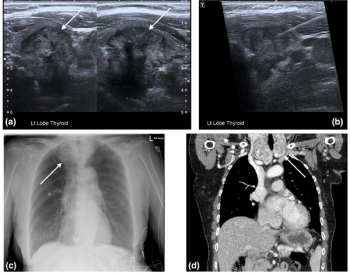

In the newly released Lung-RADS 2022 classification system for computed tomography (CT) lung cancer screening, the American College of Radiology (ACR) has noted a variety of updates including new classification criteria for atypical pulmonary cysts and airway nodules, time intervals for nodule growth and a new stepped management approach for Lung-RADS categories 3 and 4A.